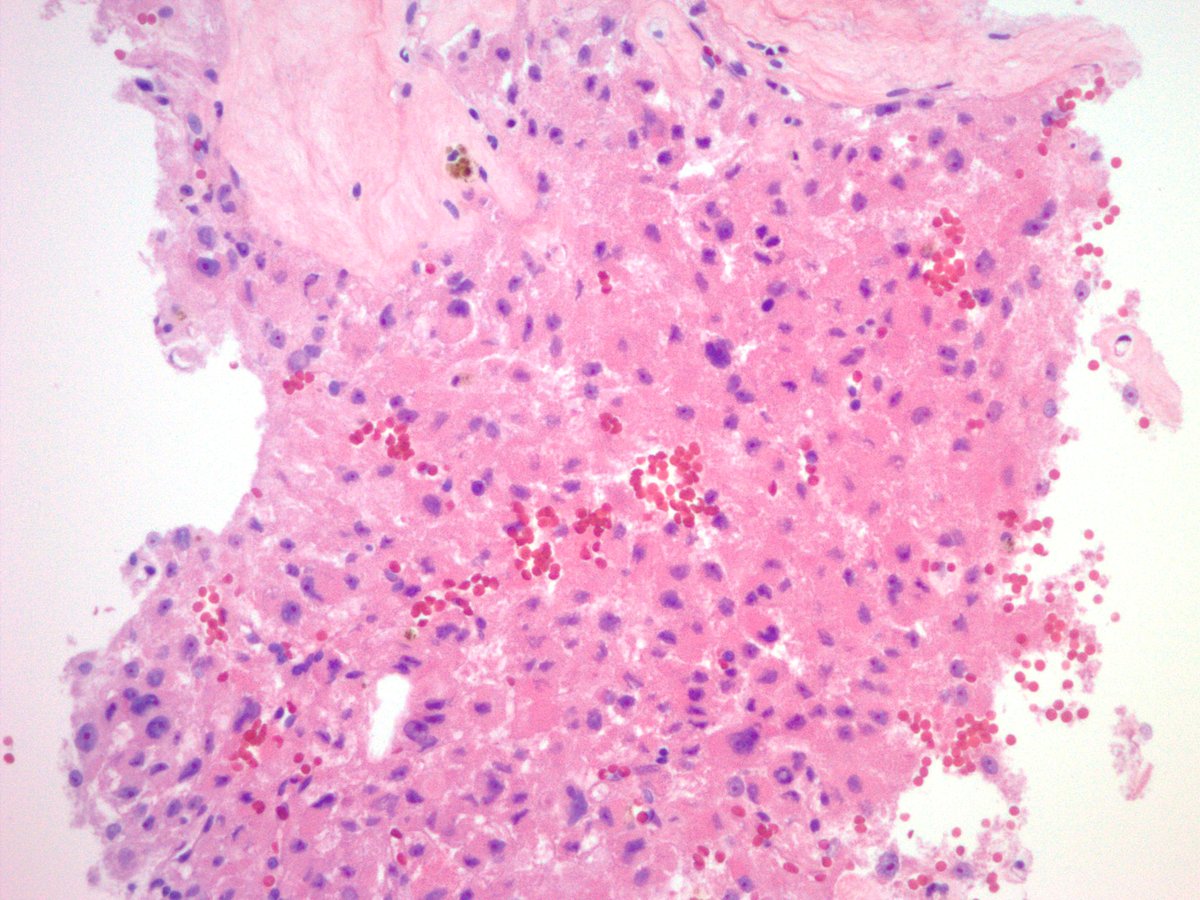

Biopsy of an incidentally discovered 5 cm well-circumscribed retroperitoneal mass abutting the bladder in a middle aged adult. Does anyone want to hazard a guess before I show the IHC? #BSTpath #pathology

jake_bledsoe's tweet image. Biopsy of an incidentally discovered 5 cm well-circumscribed retroperitoneal mass abutting the bladder in a middle aged adult. Does anyone want to hazard a guess before I show the IHC? #BSTpath #pathology